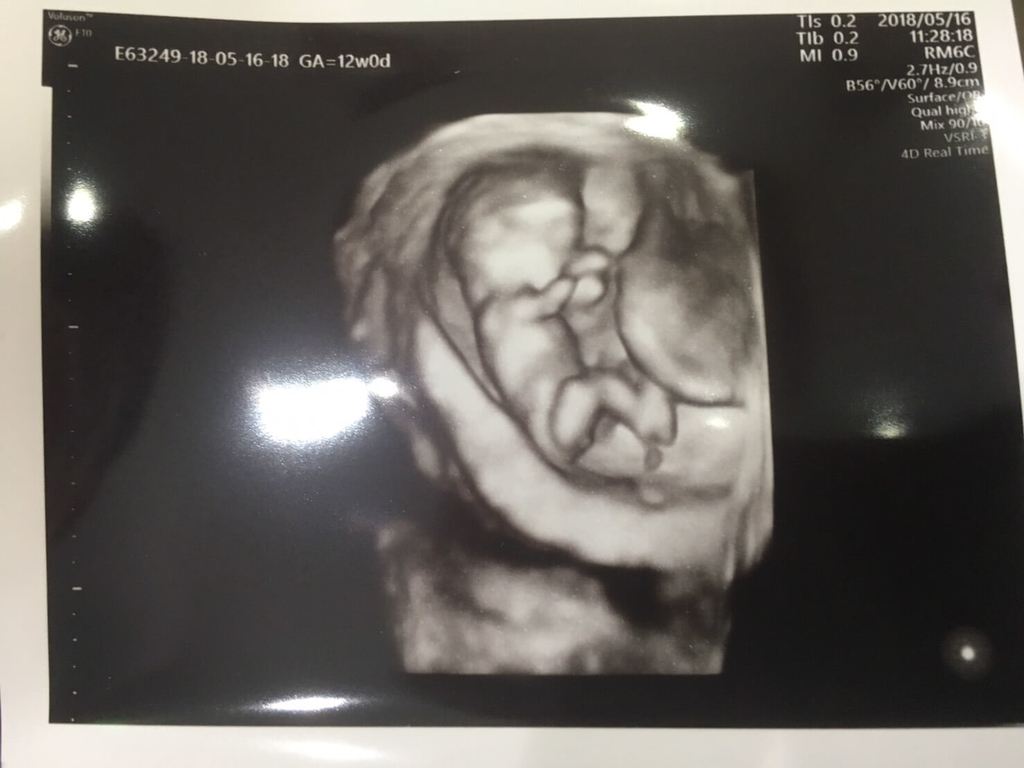

毎回妊婦健診は2人で行って、祭人の調子や様子を見てくるんだけど、いつも病院にはお母さんだけで、少し悲しくなると同時に、自分はいつも一緒に行ける父でよかったと誇りに思ってる。

いつもすくすく元氣に育っていく祭人の様子を、間近で友希と一緒に見れることが何より嬉しくて。